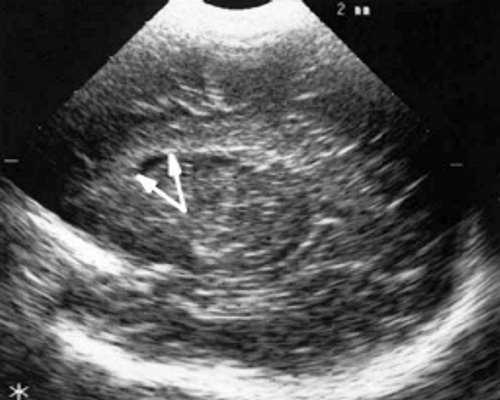

У детей этой группы при первом эхоэнцефалографическом исследовании были выявлены субэпендимально расположенные кистозные структуры на уровне таламо-каудальной вырезки (ТКВ) и (или) кпереди от нее диаметром от 0,3 до 1,1 см. У части новорожденных субэпендимальные кисты были представлены единой полостью с однородным или неоднородным содержимым, у других детей эти структуры напоминали соты, т. е. состояли из множества жидкостных включений, окруженных эхопозитивным ободком (рис. 3). Эти структурные особенности субэпендимальных кист, по-видимому, обусловлены разными стадиями резорбции. У 10 детей субэпендимальные кисты располагались в симметричных участках обоих полушарий, у 2 новорожденных - только в левом полушарии. У 3 детей, помимо субэпендимальных кист, расположенных в таламо-каудальной вырезке и (или) кпереди от нее, дополнительно выявлены субэпендимальные щелевидные кистозные структуры на уровне средних или передних отделов лобных рогов (см. рис. 3).

Рис. 3. Эхоэнцефалограмма ребенка Б. со смешанной герпес-цитомегаловирусной инфекцией, 5-е сут. жизни.

а) Правое полушарие. Стрелками обозначены субэпендимальные кисты, имеющие вид сот, расположенные в таламокаудальной вырезке и кпереди от нее.

б) Левое полушарие. Стрелками обозначены субэпендимальные кисты, имеющие вид сот, расположенные в таламокаудальной вырезке и кпереди от нее.